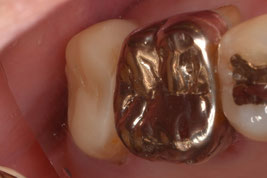

3週間後の経過観察で無事に生着していることを確認しました。歯肉の炎症も消失し、良好な経過と判断したため歯冠修復に移行しました。

近遠心的幅径を大幅に縮小させて、歯牙にかかる咬合力を軽減させると同時に、遠心部の清掃性を改善させました。